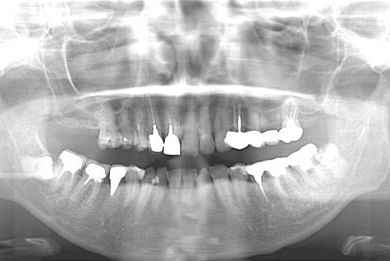

| 性別/年齢 | 女性 / 46歳 | ||||||||||||||||||||||||||||||||

| 治療内容 | メタルボンドセラミックブリッジ3本(メタルボンドセラミック用土台1本)、オールセラミック5本(オールセラミック用土台4本)、オールセラミックラミネートベニア2本 | ||||||||||||||||||||||||||||||||

| 治療期間 | 9ヶ月 |